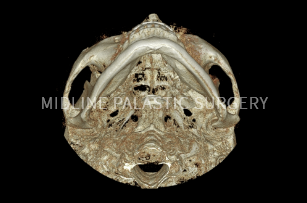

첫째, 3D-CT로 얼굴 뼈 촬영

둘째, CT, X-ray로 얼굴 뼈 전체 분석

셋째, 개개인에 맞는 섬세한 수술 계획

CT 촬영

3D-CT로 촬영한 데이터를 기반으로 얼굴뼈

전체를 정밀하게 분석하여 보다 안전하고

정확한 수술 계획이 가능합니다.